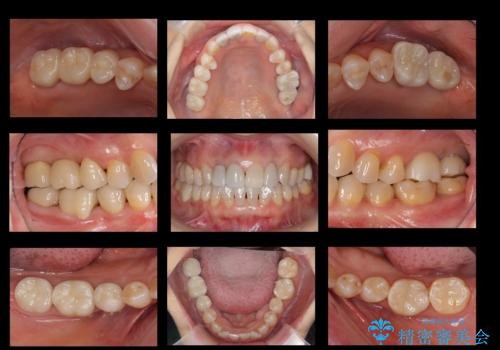

全体的にしっかり治療を行い、メンテナンスにはいることができました。

- 前歯のかぶせ物のやりかえと、全体的な治療をご希望して来院。

全体的にプラスチックで治療してあり、劣化していたのと、また、右上6番は根の治療がされていましたがプラスチックで埋めてあるだけで中を見たところ残念ながら割れていました。その歯は抜歯し⑤6⑦ブリッジにしています。